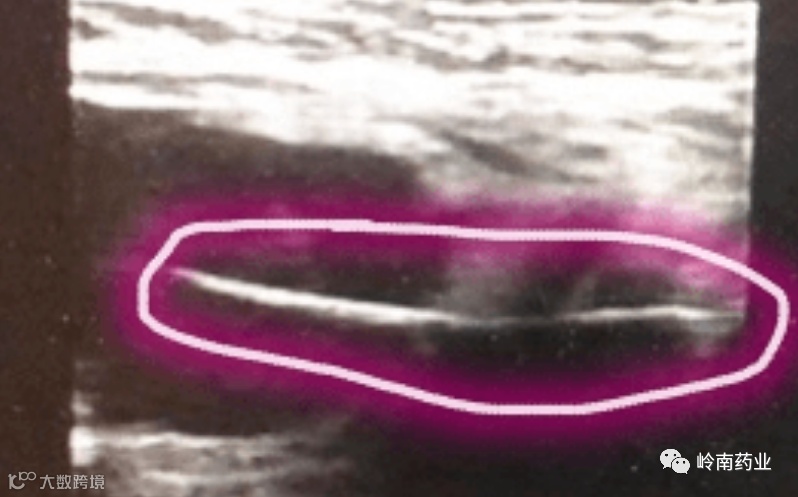

B超进一步检查显示,这个长条状的异物 一半在肝里,一半在肠子里,长约4.2厘米,像大半个牙签那么长。

(B超影像,圆圈内为异物)

“该异物横穿肝和肠子,而且是细长型,我的第一感觉是鱼刺。仔细询问,他说前几天吃过鱼,所以 高度怀疑是鱼刺扎破肠子,刺入肝内。”刘颖培医生如此判断。